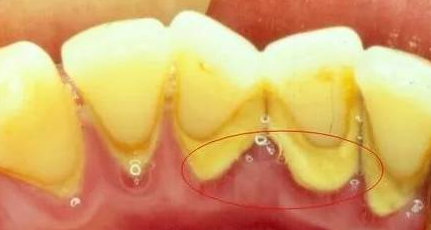

在我們的日常生活中,很少有人會意識到,小小的牙結石竟可能對口腔健康產生如此深遠的影響。牙結石是牙齒表面硬化的菌斑,它不僅是口腔衛生不佳的標志,更是牙齦疾病的重要誘因之一。珠海六和口腔醫院帶大家了解牙結石和牙齦疾病之間的關系對于預防和治療這些常見問題至關重要。

牙結石的形成始于食物殘渣和細菌在牙齒表面形成的軟性菌斑。如果未能及時清除,這種菌斑會逐漸礦化,變硬成為牙結石。牙結石一旦形成,就很難通過刷牙或使用牙線去除,通常需要專業的牙科清潔才能徹底消除。

牙結石如何導致牙齦疾病

牙結石為細菌提供了一個理想的棲息地,使其能夠持續地攻擊牙齦組織。當牙齦長期暴露于這些有害細菌及其毒素之下時,可能會引發炎癥反應,即牙齦炎。如果不加以控制,牙齦炎可以進一步發展成更為嚴重的牙周病,這可能導致牙齦退縮、牙齒松動甚至脫落。